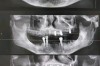

种植牙的3D过程是指利用三维数字成像技术(主要是锥形束CT扫描)和计算机辅助设计/制造(CAD/CAM)技术,对整个种植牙过程进行数字化规划和精准执行,这大大提高了种植牙的精准性、安全性、可预测性和患者舒适度,以下是种植牙3D过程的详细步骤...